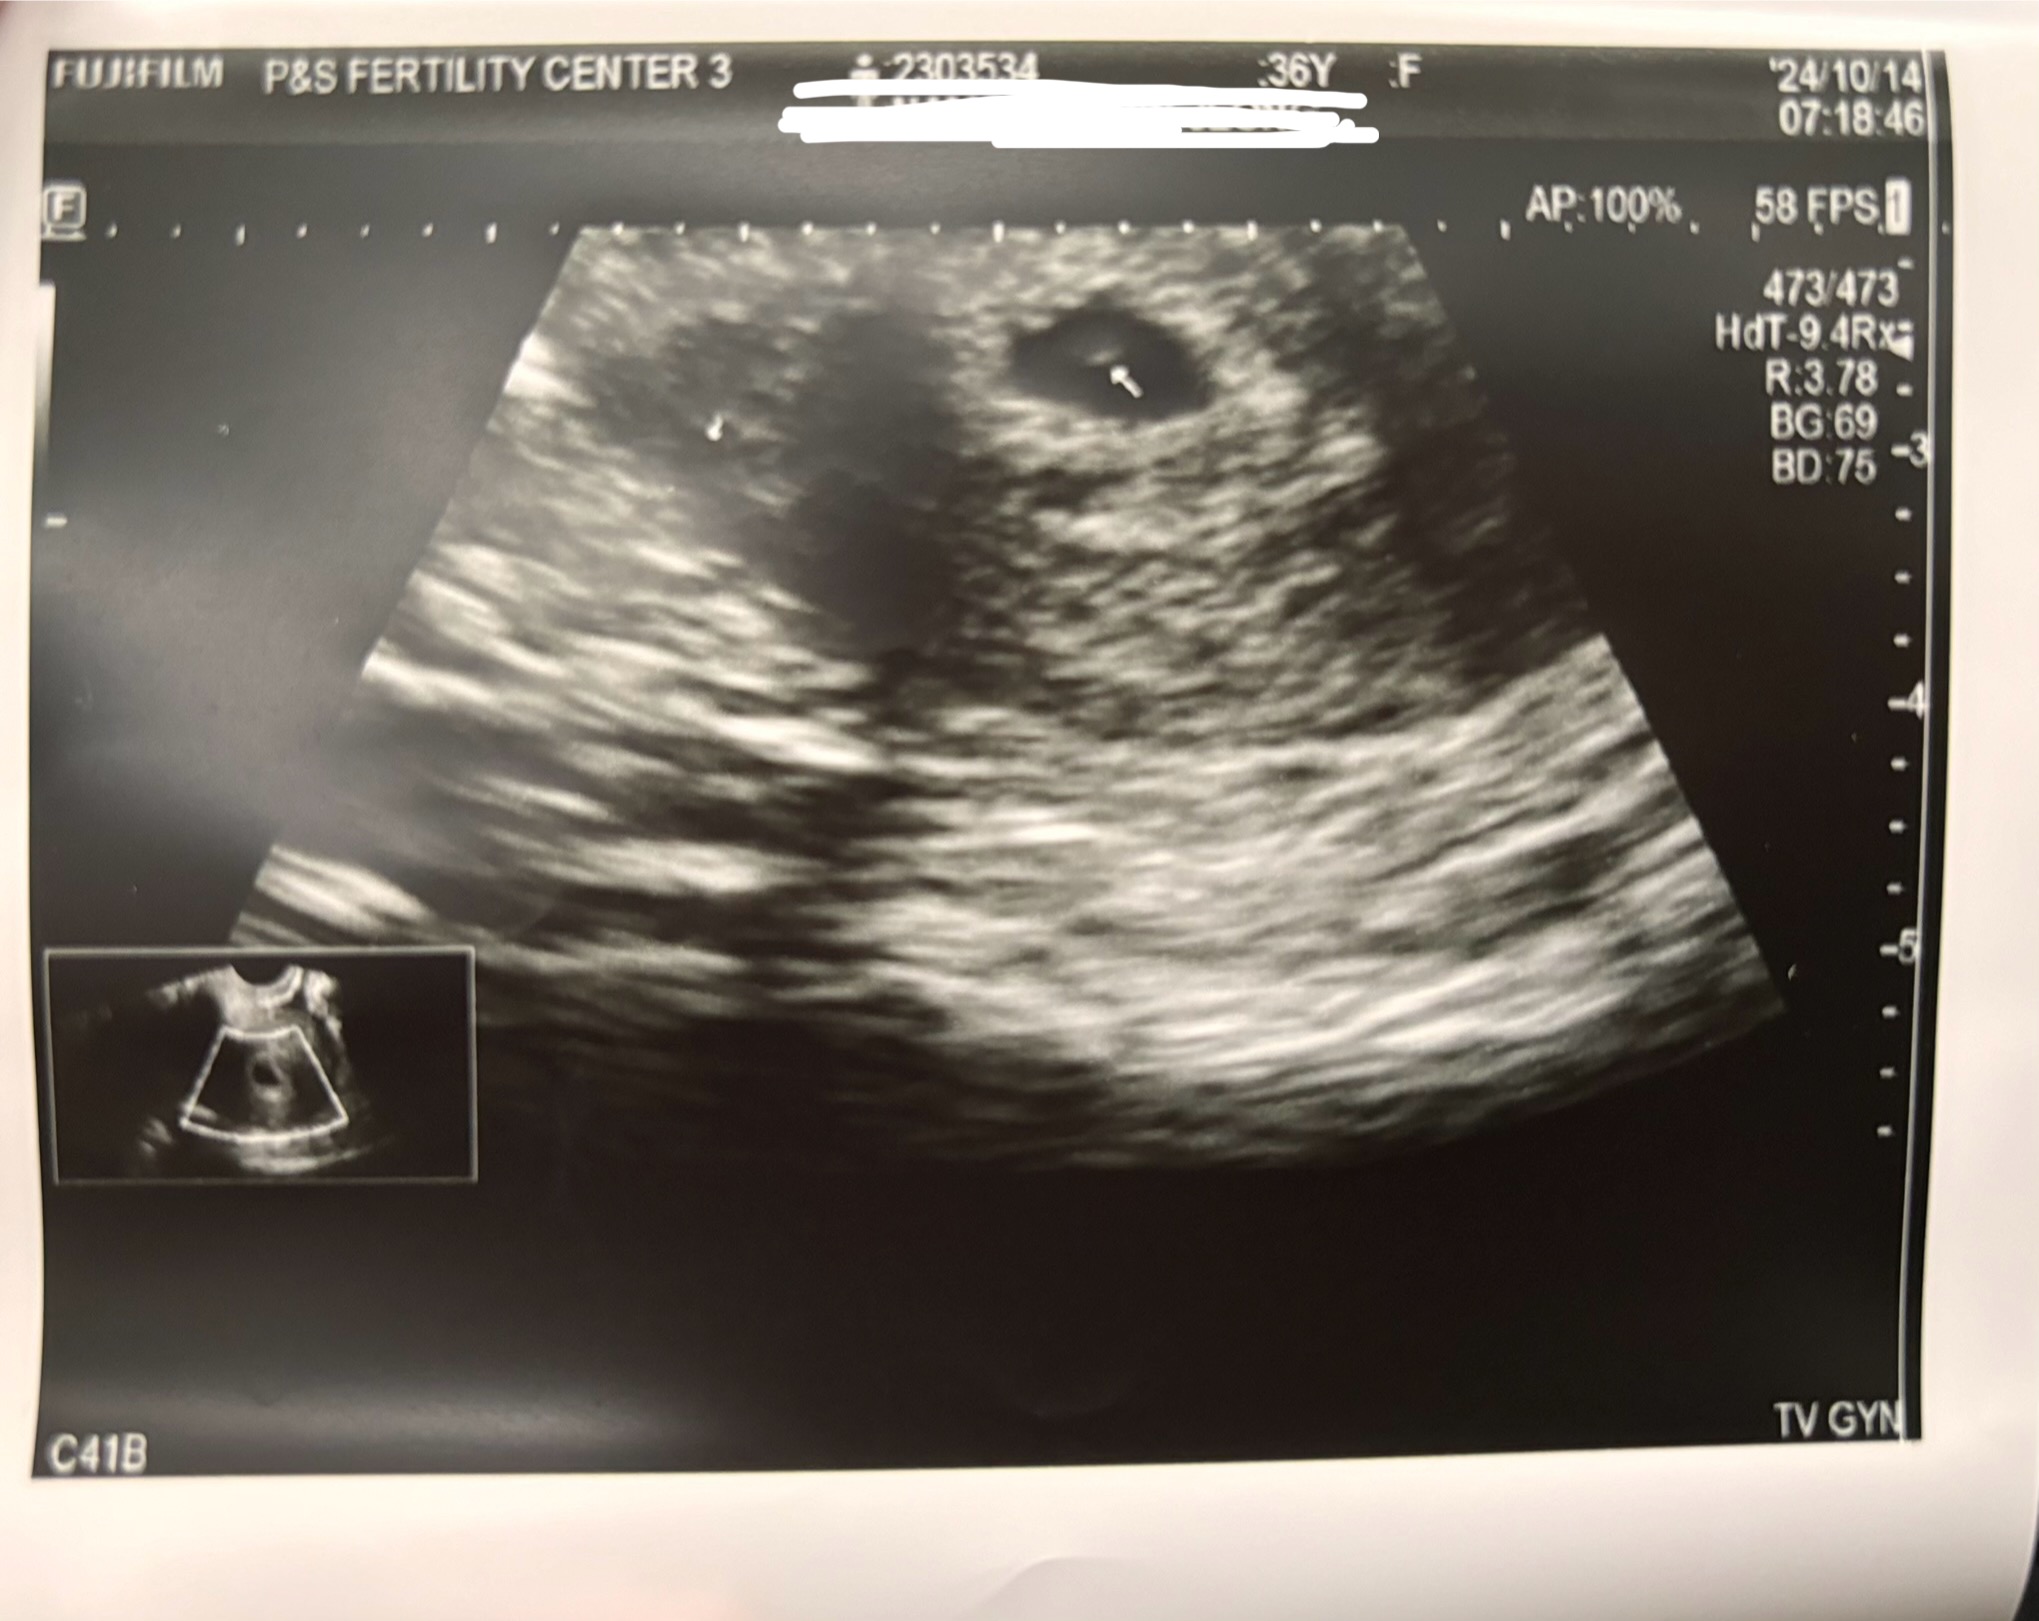

많은 분들이 궁금해하시는 ‘임신 극초기’는 일반적으로 수정이 일어난 후 1주차부터 약 6-7주차까지, 즉 다음 생리 예정일 전후까지를 의미해요. 이 시기는 아직 병원 초음파에서도 확인이 어려운 경우가 많지만, 몸에서는 아주 미세한 변화들이 시작되죠. 대부분은 생리가 예정대로 오지 않거나, 생리 전과 다른 미묘한 증상들로 임신을 의심하게 돼요.

혹시 증상이 의심된다면, 조심스럽게 테스트기를 사용해보시고, 병원에 가서 확인 받는 것도 추천드려요. 무엇보다도, 내 몸을 믿고 천천히 변화를 받아들이는 게 제일 중요하답니다.

| [난임일기] 시험관수술 이식후 첫초음파검사 (2) | 2023.12.31 |